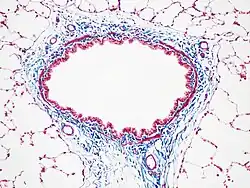

Trichrom-Färbung

Die Trichrom-Färbung ist eine Methode zur Färbung von Zellen und Geweben mit drei Farbstoffen (Chromophoren).